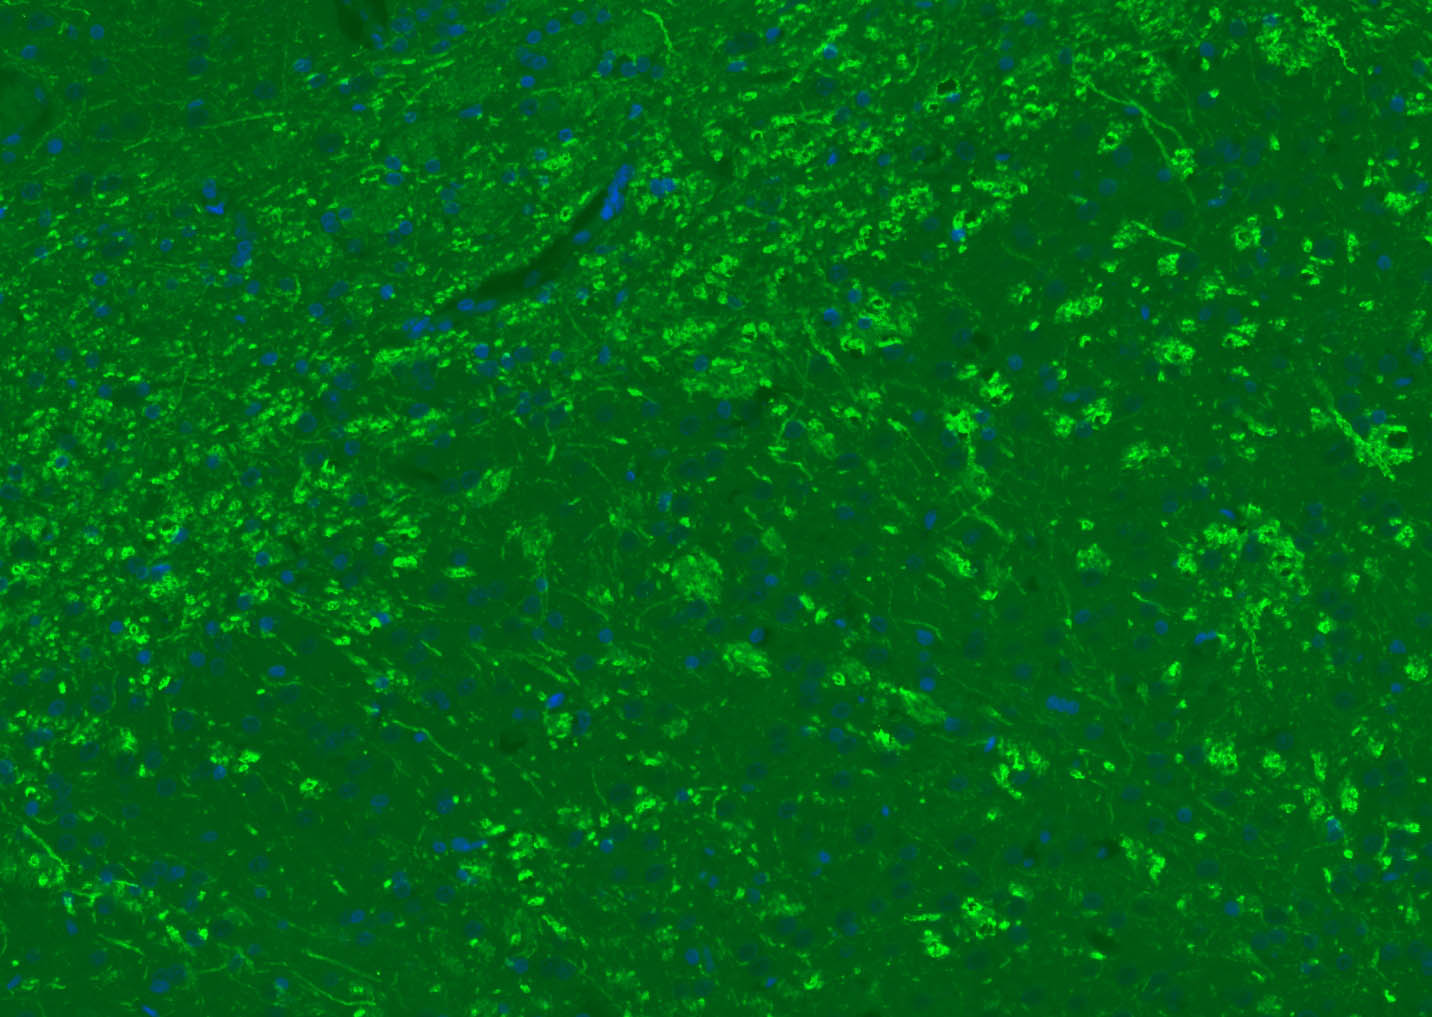

The protein encoded by the classic MBP gene is a major constituent of the myelin sheath of oligodendrocytes and Schwann cells in the nervous system. However, MBP-related transcripts are also present in the bone marrow and the immune system. These mRNAs arise from the long MBP gene (otherwise called "Golli-MBP") that contains 3 additional exons located upstream of the classic MBP exons. Alternative splicing from the Golli and the MBP transcription start sites gives rise to 2 sets of MBP-related transcripts and gene products. The Golli mRNAs contain 3 exons unique to Golli-MBP, spliced in-frame to 1 or more MBP exons. They encode hybrid proteins that have N-terminal Golli aa sequence linked to MBP aa sequence. The second family of transcripts contain only MBP exons and produce the well characterized myelin basic proteins. This complex gene structure is conserved among species suggesting that the MBP transcription unit is an integral part of the Golli transcription unit and that this arrangement is important for the function and/or regulation of these genes.

| IF | Human, Mouse, Rat | Rabbit, Pig, Sheep, Cow, Dog, Horse | 1:500-2000 |